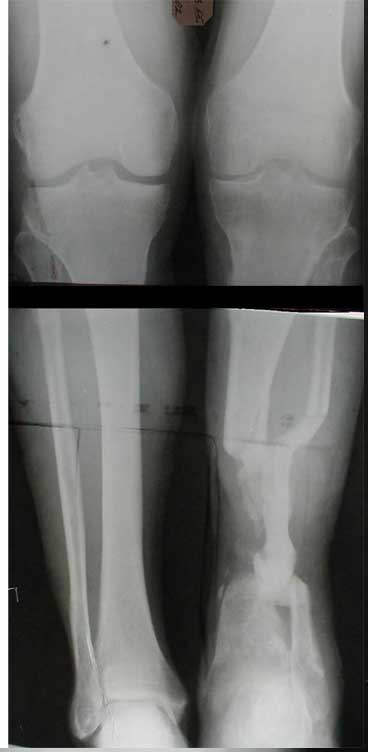

В приложении - моё наблюдение (возможно, уже представлял, тогда

извините).

Нога попала в пресс.

Ко мне больной попал черз 1,5-2 года после травмы и нескольких

операций с синегнойной инфекцией на всю голень. Меня пригласили на консультацию

насчет ампутации.

Лечил я его месяцев 8.

Малоберцовка полностью перестроилась, нога опороспособна.

При ходьбе на дальние расстояния пользуется тростью.

Осталась трофическая язва, периодически закрывается.

Клинические снимки где-то есть, но не очень качественные.

Один из вариантов.

С уважением Александр Артемьев